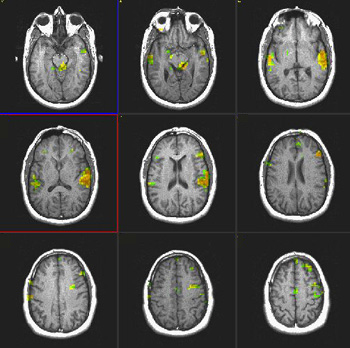

Verbal Comprehension

Right-handed volunteer, 32 year-old-man |

| Paradigm |

ON: Listening to a story

OFF: Concentrate on the back ground noise |

| Statistics |

| Statistical method |

P Value |

Z score |

| T-Test |

0.0001 |

3.8 |

| Activation |

Left hemisphere activation is clearly greater. The activation is in the following areas: Broca's (image 5), Wernike's (images 4 and 5), left supramarginal gyrus (heteromodal associative area, in image 5), left motor and premotor strip. The primary auditory areas are also activated predominantly on the left. |